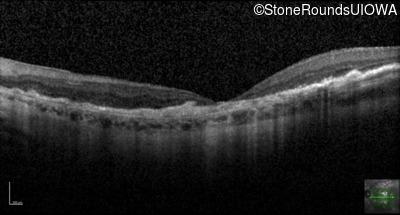

Age at visit: 64 years

This 64 year old woman first noticed some distortion in her vision at age 46 while looking at graph paper.